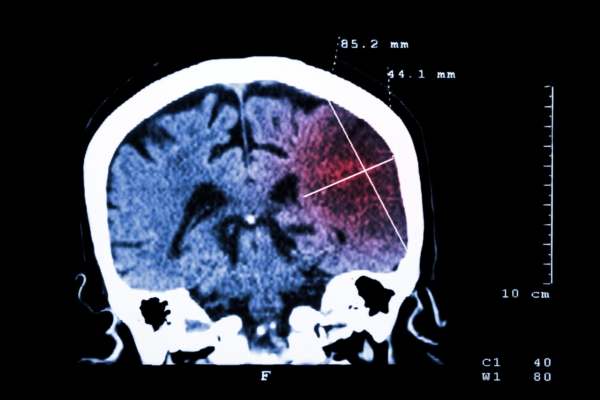

The risk of stroke and heart problems is reduced with an optimistic attitude in older adults. The study found that a predominantly pessimistic outlook on life raises one’s risk of death from heart disease. The study involved nearly 3,000 participants tracked for 11 years. The researchers found that the most pessimistic participants were twice as ...click here to read more